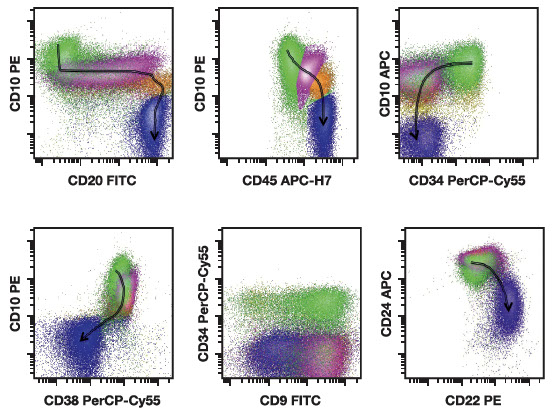

Normal B-cell maturation in the bone marrow. All plots show CD19-positive cells in a normal marrow specimen. Arrows follow changes in antigen expression with maturation from an early hematogone to a mature naive B cell. The earliest hematogones (stage 1) or B-cell precursors are shown in green and express strong CD10 with CD34 and CD38 with low CD45 without CD20. As B cells progress to stage 2 or intermediate-stage hematogones (shown in mauve), they drop CD34, and the level of CD38 increases slightly while CD10 and CD45 decrease and CD20 slowly increases. With progression to prenaive immature B cells or stage 3 hematogones (shown in orange), these cells continue to decrease expression of CD10 and acquire higher levels CD20 and CD45. With progression to mature B cells, CD20 and CD45 are acquired at high levels while CD10 and CD38 are lost. Note that B-cell markers CD24 and CD22 vary in intensity in a reciprocal way during this transition, with mature B cells expressing strong CD22 with low CD24 [18]